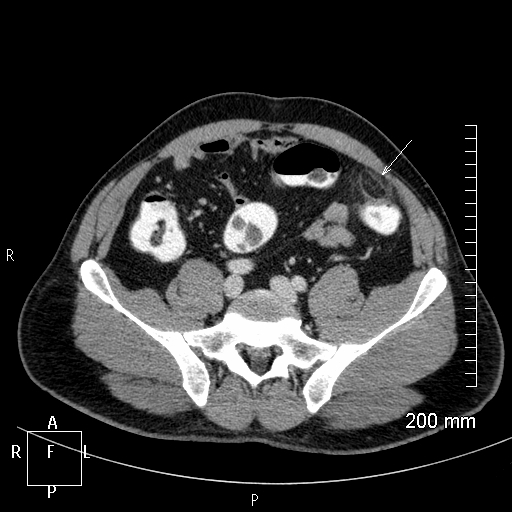

Q

Homme 50 ans, violentes douleurs abdominales et syndrome occlusif, un TDM est réalisé. Diagnostic?

A

Invaginaton Intestinale aiguë